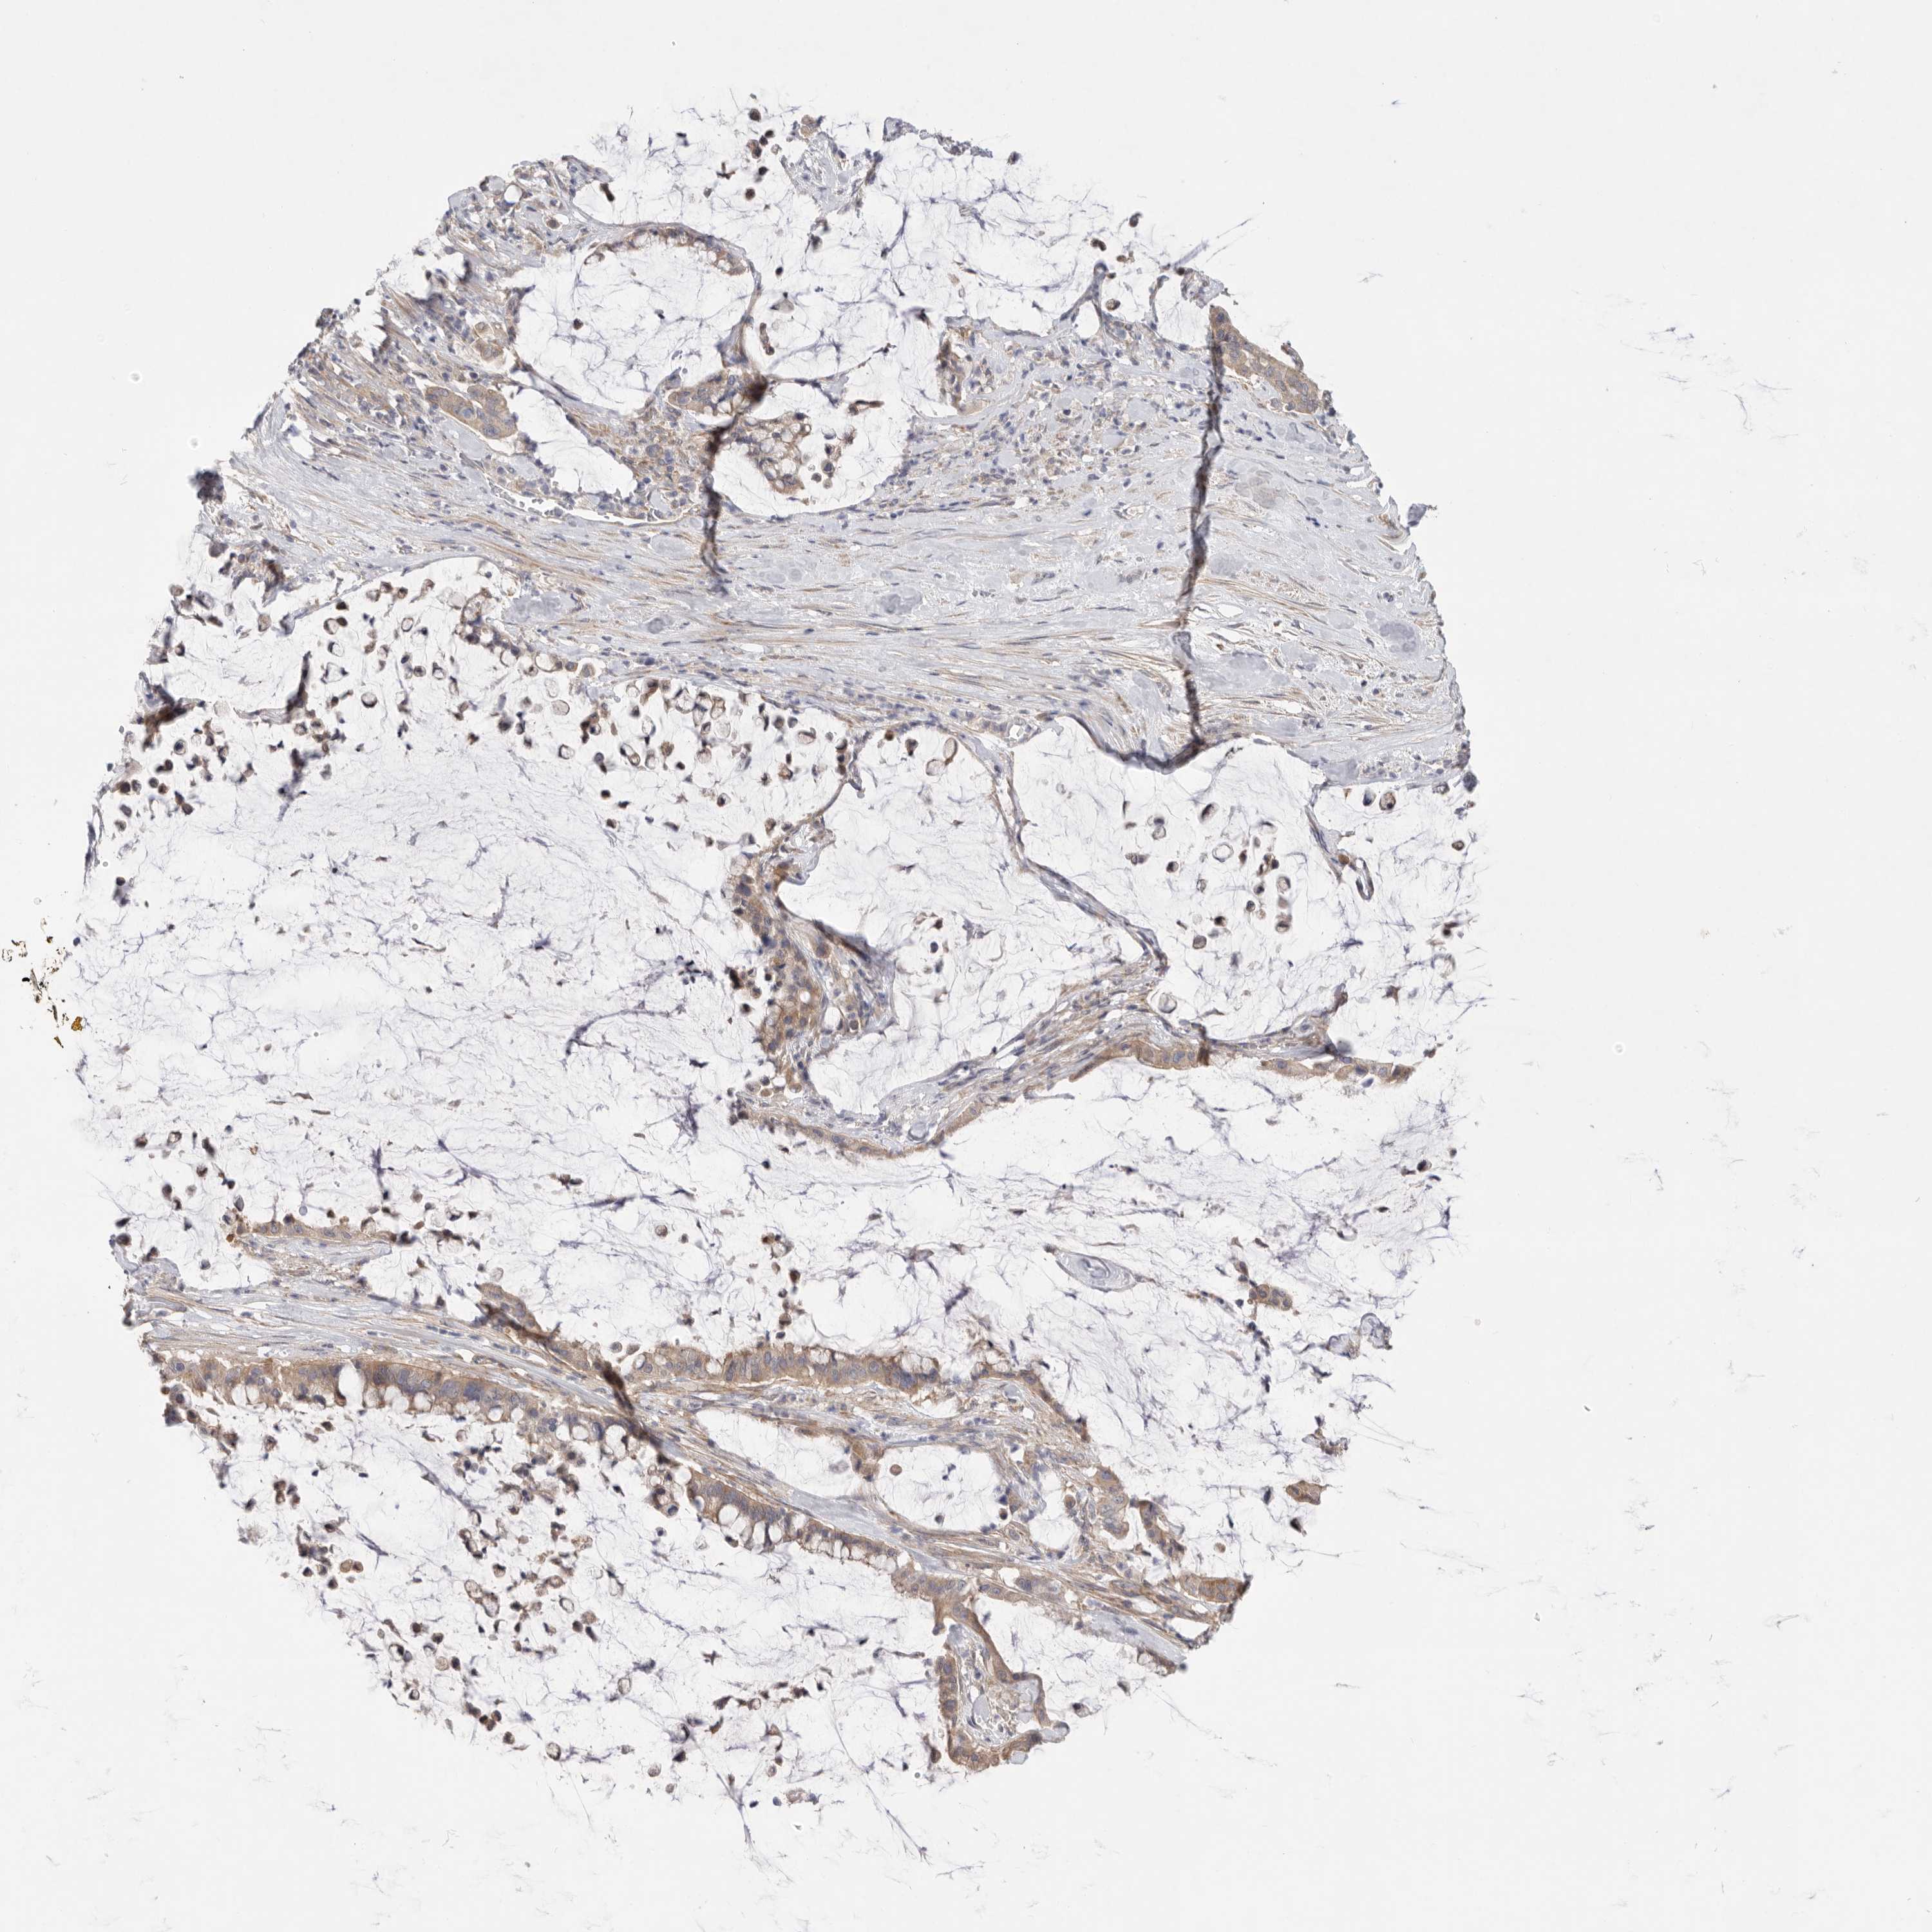

PANCREATIC CANCER - Protein expressioni

A mouse-over function shows sample information and annotation data. Click on an image to view it in a full screen mode. Samples can be filtered based on level of antibody staining by selecting one or several of the following categories: high, medium, low and not detected. The assay and annotation is described here.

Note that samples used for immunohistochemistry by the Human Protein Atlas do not correspond to samples in the TCGA dataset.

Antibody stainingi

Antibody staining in the annotated cell types in the current human tissue is reported as not detected, low, medium, or high, based on conventional immunohistochemistry profiling in selected tissues. This score is based on the combination of the staining intensity and fraction of stained cells.

Each image is clickable and will lead to virtual microscopy that enables deeper exploration of all samples and also displays staining intensity scores, fraction scores and subcellular localization as well as patient and tissue information for each sample.

Antibody HPA027124

Antibody HPA027130

Staining

High

Medium

Low

Not detected

Intensity

Strong

Moderate

Weak

Negative

Quantity

>75%

75%-25%

<25%

None

Location

Nuclear

Cytoplasmic/membranous

Cytoplasmic/membranous,nuclear

Adenocarcinoma, NOS